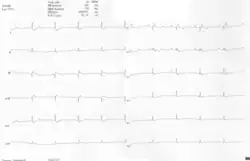

ECGs recorded during sinus rhythm and AVRT in a 9-year-old girl with Ebstein's anomaly and a Mahaim accessory pathway.

A 12-lead ECG of a woman with Ebstein's anomaly: The ECG shows signs of right atrial enlargement, best seen in V1. Other P waves are broad and tall, these are termed "Himalayan" P waves. Also, a right bundle-branch block pattern and a first-degree atrioventricular block (prolonged PR-interval) due to intra-atrial conduction delay are seen. No evidence of a Kent-bundle is seen in this patient. The T wave inversion in V1-4 and a marked Q wave in III occur; these changes are characteristic for Ebstein's anomaly and do not reflect ischemic ECG changes in this patient.

Other abnormalities that can be seen on the ECG include:

1. signs of right atrial enlargement or tall and broad 'Himalayan' P waves

2. first degree atrioventricular block manifesting as a prolonged PR-interval[7]

3. low amplitude QRS complexes in the right precordial leads

4. atypical right bundle branch block

5. T wave inversion in V1-V4 and Q waves in V1-V4 and II, III and aVF.[8]